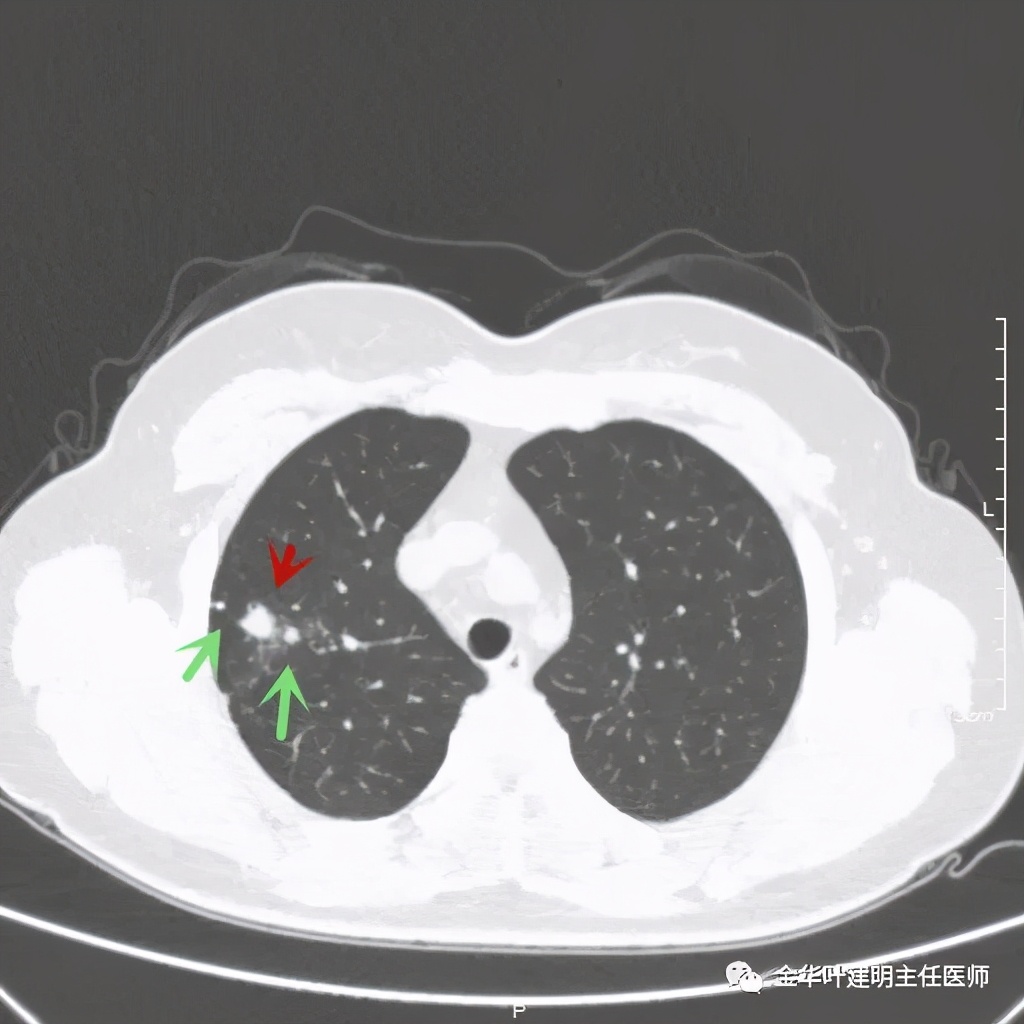

绿色箭头示主病灶边有小的实性微小结节,主病灶边缘非常光滑,没有毛刺、分叶等征

主病灶光滑,旁边有不清爽的小斑点状病灶